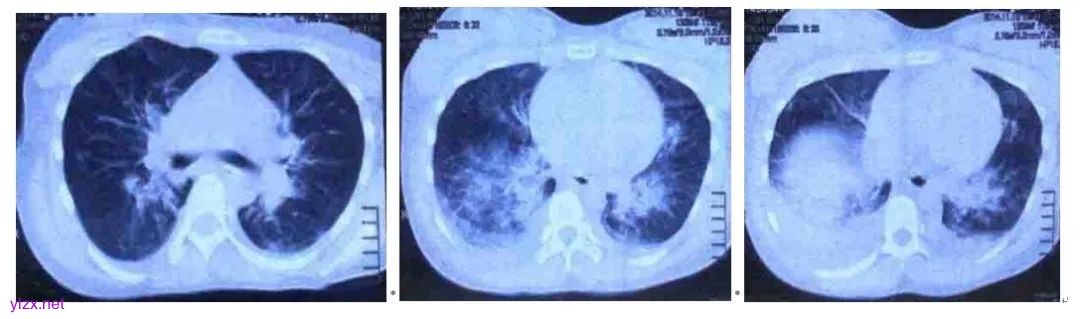

胸部CT:双肺上叶多发增厚的小叶间隔,双侧胸腔积液,双肺下叶节段性膨胀不全,多发感染性病变,肺门增大,双肺内带片状致密影,不除外肺水肿可能(图1)。

图1 胸部CT